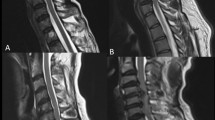

A total of 56 early CSM patients and 56 matched volunteers were included in the study, forming a total of 56 case-matched groups (1:1 matching). The basic clinical information and spinal location distribution are detailed in Table 2. Conventional imaging and dMRI variable colour maps of paired volunteers and CSM patients are shown in Fig. 3.

Conventional imaging and dMRI variable colour maps of patients with CSM occurring at C5–C6 and matched volunteers. a The volunteers and b the matched CSM patients. Rows 1–3 of the right picture represent the colour maps of different DTI, DKI, and NODDI variables, respectively. The colour maps of the variable are manually adjusted to show the clearest image contrast. In a, the FA value is 0.0955, the MD value is 0.0001, the AD value is 0.0003, the RD value is 0.0002, the MK value is 0.2163, the AK value is 0.0753, the RK value is 0.4833, the ISOVF value is 0.1388, and the ODI value is 0.0129. The NDI value is 0.1306 and the AWF value is 0.0525; in b, the FA value is 0.0892, the MD value is 0.0001, the AD value is 0.0002, the RD value is 0.0002, the MK value is 0.2155, the AK value is 0.0701, and the RK value is 0.0721. The ISOVF value is 0.1616, the ODI value is 0.0722, the NDI value is 0.1211, and the AWF value is 0.01012